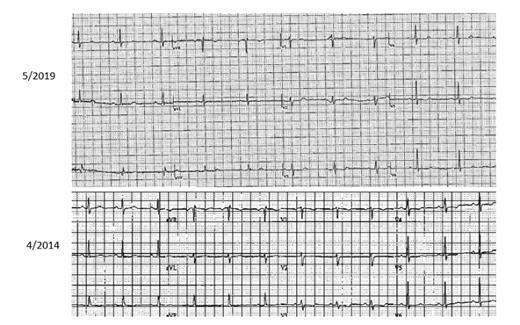

The current electrocardiogram (ECG) on top (May 2019) after ibrutinib is withheld for at least two weeks. The ECG on the bottom (April 2014) precedes the initiation of ibrutinib initially. No significant changes are noted between these two tracings.

The question of whether ibrutinib is causative of atrial fibrillation has been the subject of much discussion and investigation. Several articles have suggested that it might occur quite frequently in patients with CLL, in one study up to 13 percent,1 and the consequences of atrial fibrillation in patients who were on ibrutinib resulted in a high percentage having to discontinue therapy, most commonly owing to an increase in bleeding events.2 It is very clear that ibrutinib therapy is associated with a higher rate of atrial fibrillation than the “ambient” rate found in patients with CLL who are not on that therapy, and the risk of bleeding is a particularly vexing problem that may lead to discontinuation of this treatment.3,4 What is particularly challenging in this case is whether ibrutinib is associated with a more serious and life threatening rhythm disturbance than just atrial fibrillation. As it turned out, in this patient, there was an episode of sudden death in which she was quickly and effectively resuscitated. This is very good news; however, from a detailed history and extensive evaluation, the cause of ventricular tachycardia or ventricular fibrillation (VT/VF) was not apparent. She had no structural reason for VT (normal left ventricular ejection fraction and normal valvular structures) but was on ibrutinib and dextroamphetamine-amphetamine (a powerful stimulant). She did have significant alcohol exposure, and that certainly may have contributed. Her baseline electrocardiogram in 2014 and the repeat after the event in May 2019 did not reveal any major abnormalities other than nonspecific anterior T wave changes (Figure 1). When a topical wireless monitor was placed, the QT interval appeared prolonged and varied significantly when accessed via the transmission (Figure 2, black arrows). It has been observed that ibrutinib may be associated with VT, but it is not clear that it is a prolonged QT-based mechanism.5-7 Furthermore, this patient had not been on ibrutinib for more than two weeks on the May 2019 ECG or when the wireless monitor was placed.